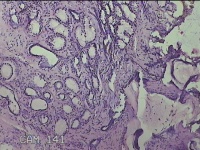

左侧外阴囊肿壁

性别

女

年龄

35岁

临床诊断

左外阴囊肿

一般病史

发现外阴囊肿2年余,加重3月。

标本名称

大体所见

灰白暗红色囊壁样组织5.5x2.8x0.7cm一堆,表面光滑,部分已切开,囊内容物已流失,囊壁厚0.1cm。

图1

具体位置,考虑巴氏腺囊肿。